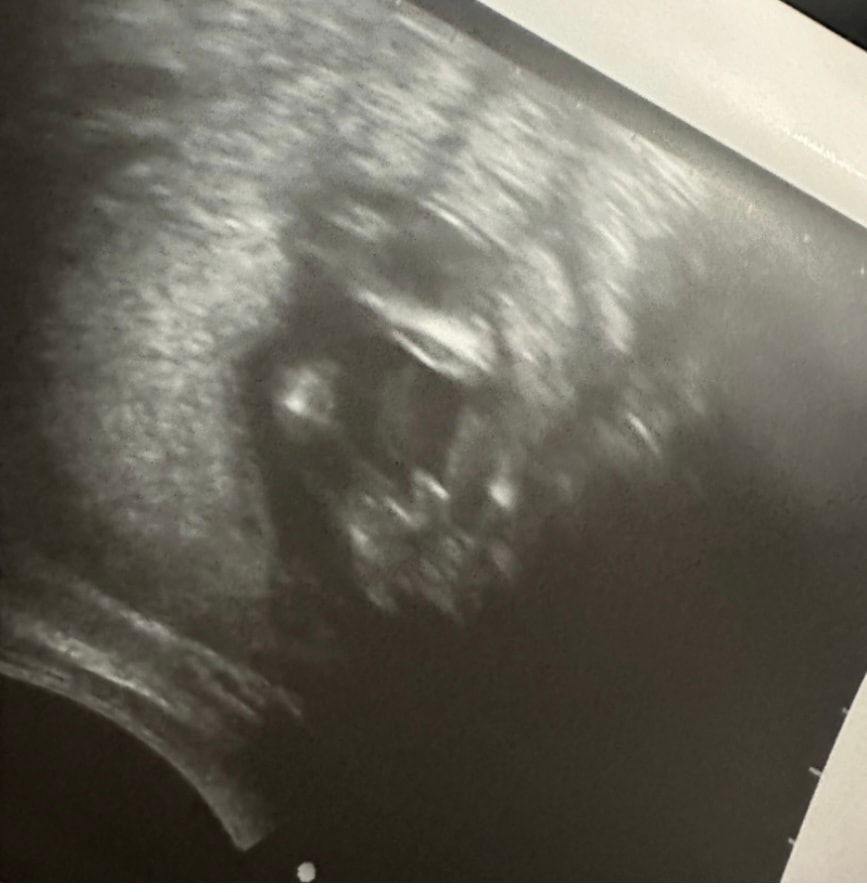

Смотрят снизу… А там🔥😂 У дочки изменились обстоятельства 😂 *где-то я здесь читала такую фразу😂

Ждём тебя, наш сынок❤️